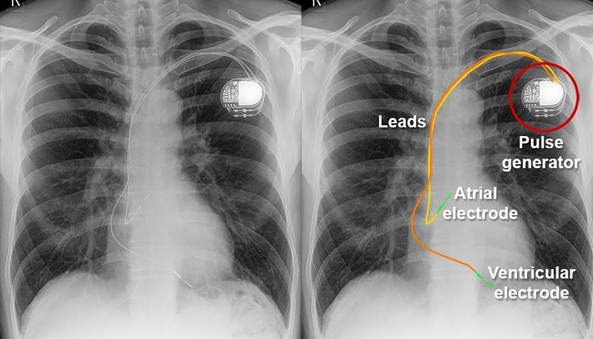

Cardiomegaly

Pacemaker Placement